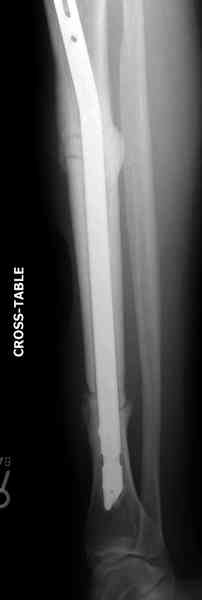

The cages are commercially available but up to 10 cm. So we measured the needed length on x-rays, added 2 cm at both ends for sure that

the resected piece will include all, and resulted with 15 cm which one was ordered and individually made by the same factory. So yes, we made the gap to fit the cage.

The inner diameter of the tube is 13 mm, the nail was 12 mm, so not so much space to put something inside. Yes, this is really shaft endoprosthesis which i hardly ever would offer for a young football player. Though... Maybe we would when we collect some experience with this sort of implants to feel/prognose its strength in different settings.

No problem with the skin since the cage is less than the removed tissue and the surgery was quick enough not to meet oedema.